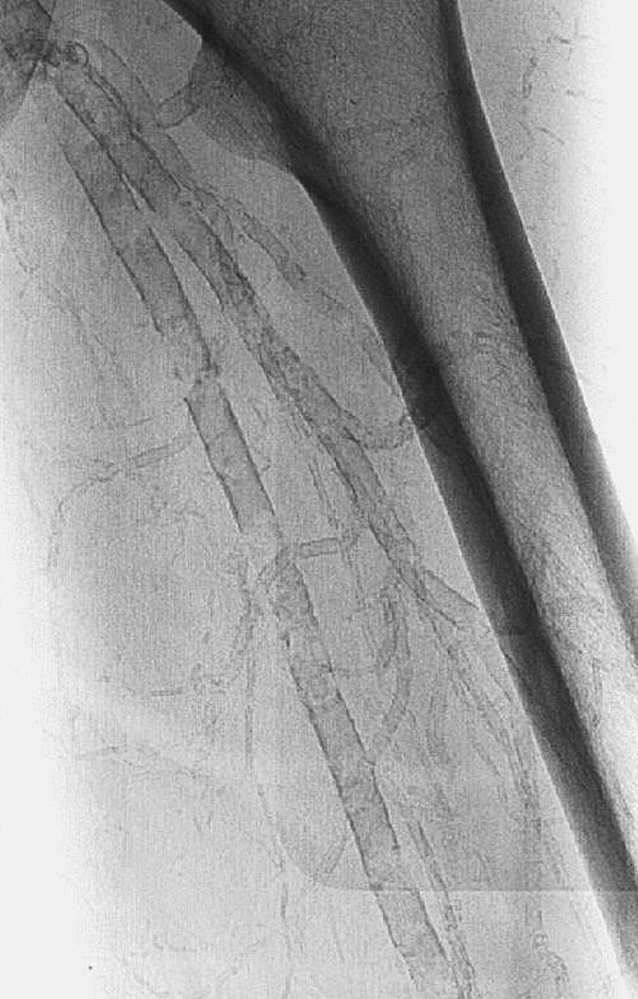

Solch eine Mediasklerose blockiert die ABI-Messung Solch eine Mediasklerose blockiert die ABI-Messung © Mediengruppe Oberfranken – Fachverlage GmbH & Co. KG, Kulmbach

Lassen sich die Fußpulse nicht tas­ten, bedeutet dies nicht unbedingt, dass eine PAVK vorliegt. Denn Fußödeme, Hautverhärtungen oder Wunden können die Tastbarkeit verringern. Um die klinische Verdachtsdiagnose abzusichern, wird deshalb zusätzlich der Knöchel-Arm-Index (Ankle-Brachial-Index, ABI) gemessen. Als pathologisch gilt ein Quotient aus Fuß- und Armarteriendruck von < 0,9. Bei einer schweren PAVK liegt der ABI < 0,5. Quotienten > 1,3 sprechen für eine zirkuläre Mediasklerose, die eine aussagekräftige Messung unmöglich macht. Sie findet man vor allem bei Patienten mit Diabetes mellitus und bei fortgeschrittener Niereninsuffizienz. Über die Höhe der Engstelle sagt der ABI nichts aus.